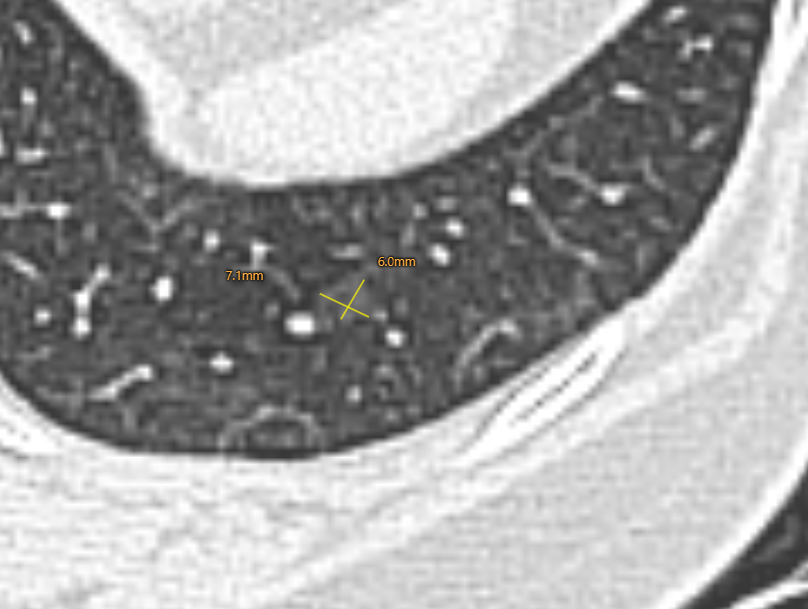

右肺下叶背段纯磨玻璃结节,最大截面约0.9cm×0.9cm,平均CT值约-431Hu,结节呈类圆形,其中可见小空泡,病灶边界清楚,与9年前CT片比较,病灶密度、大小均无明显变化,考虑为微浸润性腺癌-浸润性腺癌,以微浸润性腺癌可能性大。

答:概率不大!确实有部分磨玻璃结节在术前对良恶性的判断是有困难的,就是我常说到的不典型肺结节。类似结节其实是非常典型的,在清晰的肺野内发现的磨玻璃结节,呈类圆形(圆鼓鼓),密度相对较高,病灶境界清晰;并且灶周没有血管及支气管干扰,不是奇形怪状的,周边没有索条或者长毛刺,邻近未见卫星灶,再结合抗炎治疗或者随访过程中没有机化,属于早期肺癌的可能性非常之大。

诊断:这个结节是一个混杂密度结节,大部分以实性成分为主,周边可见毛刺及分析,由于病灶非常小,如果首次发现还是要小心,但是通过以下多次的随访和复查,我们考虑良性纤维灶的概率更高。

但是由于这个结节位于外周带,非常容易切除,因为和主病灶是同侧,所以这个结节,我么可以考虑一次处理掉。